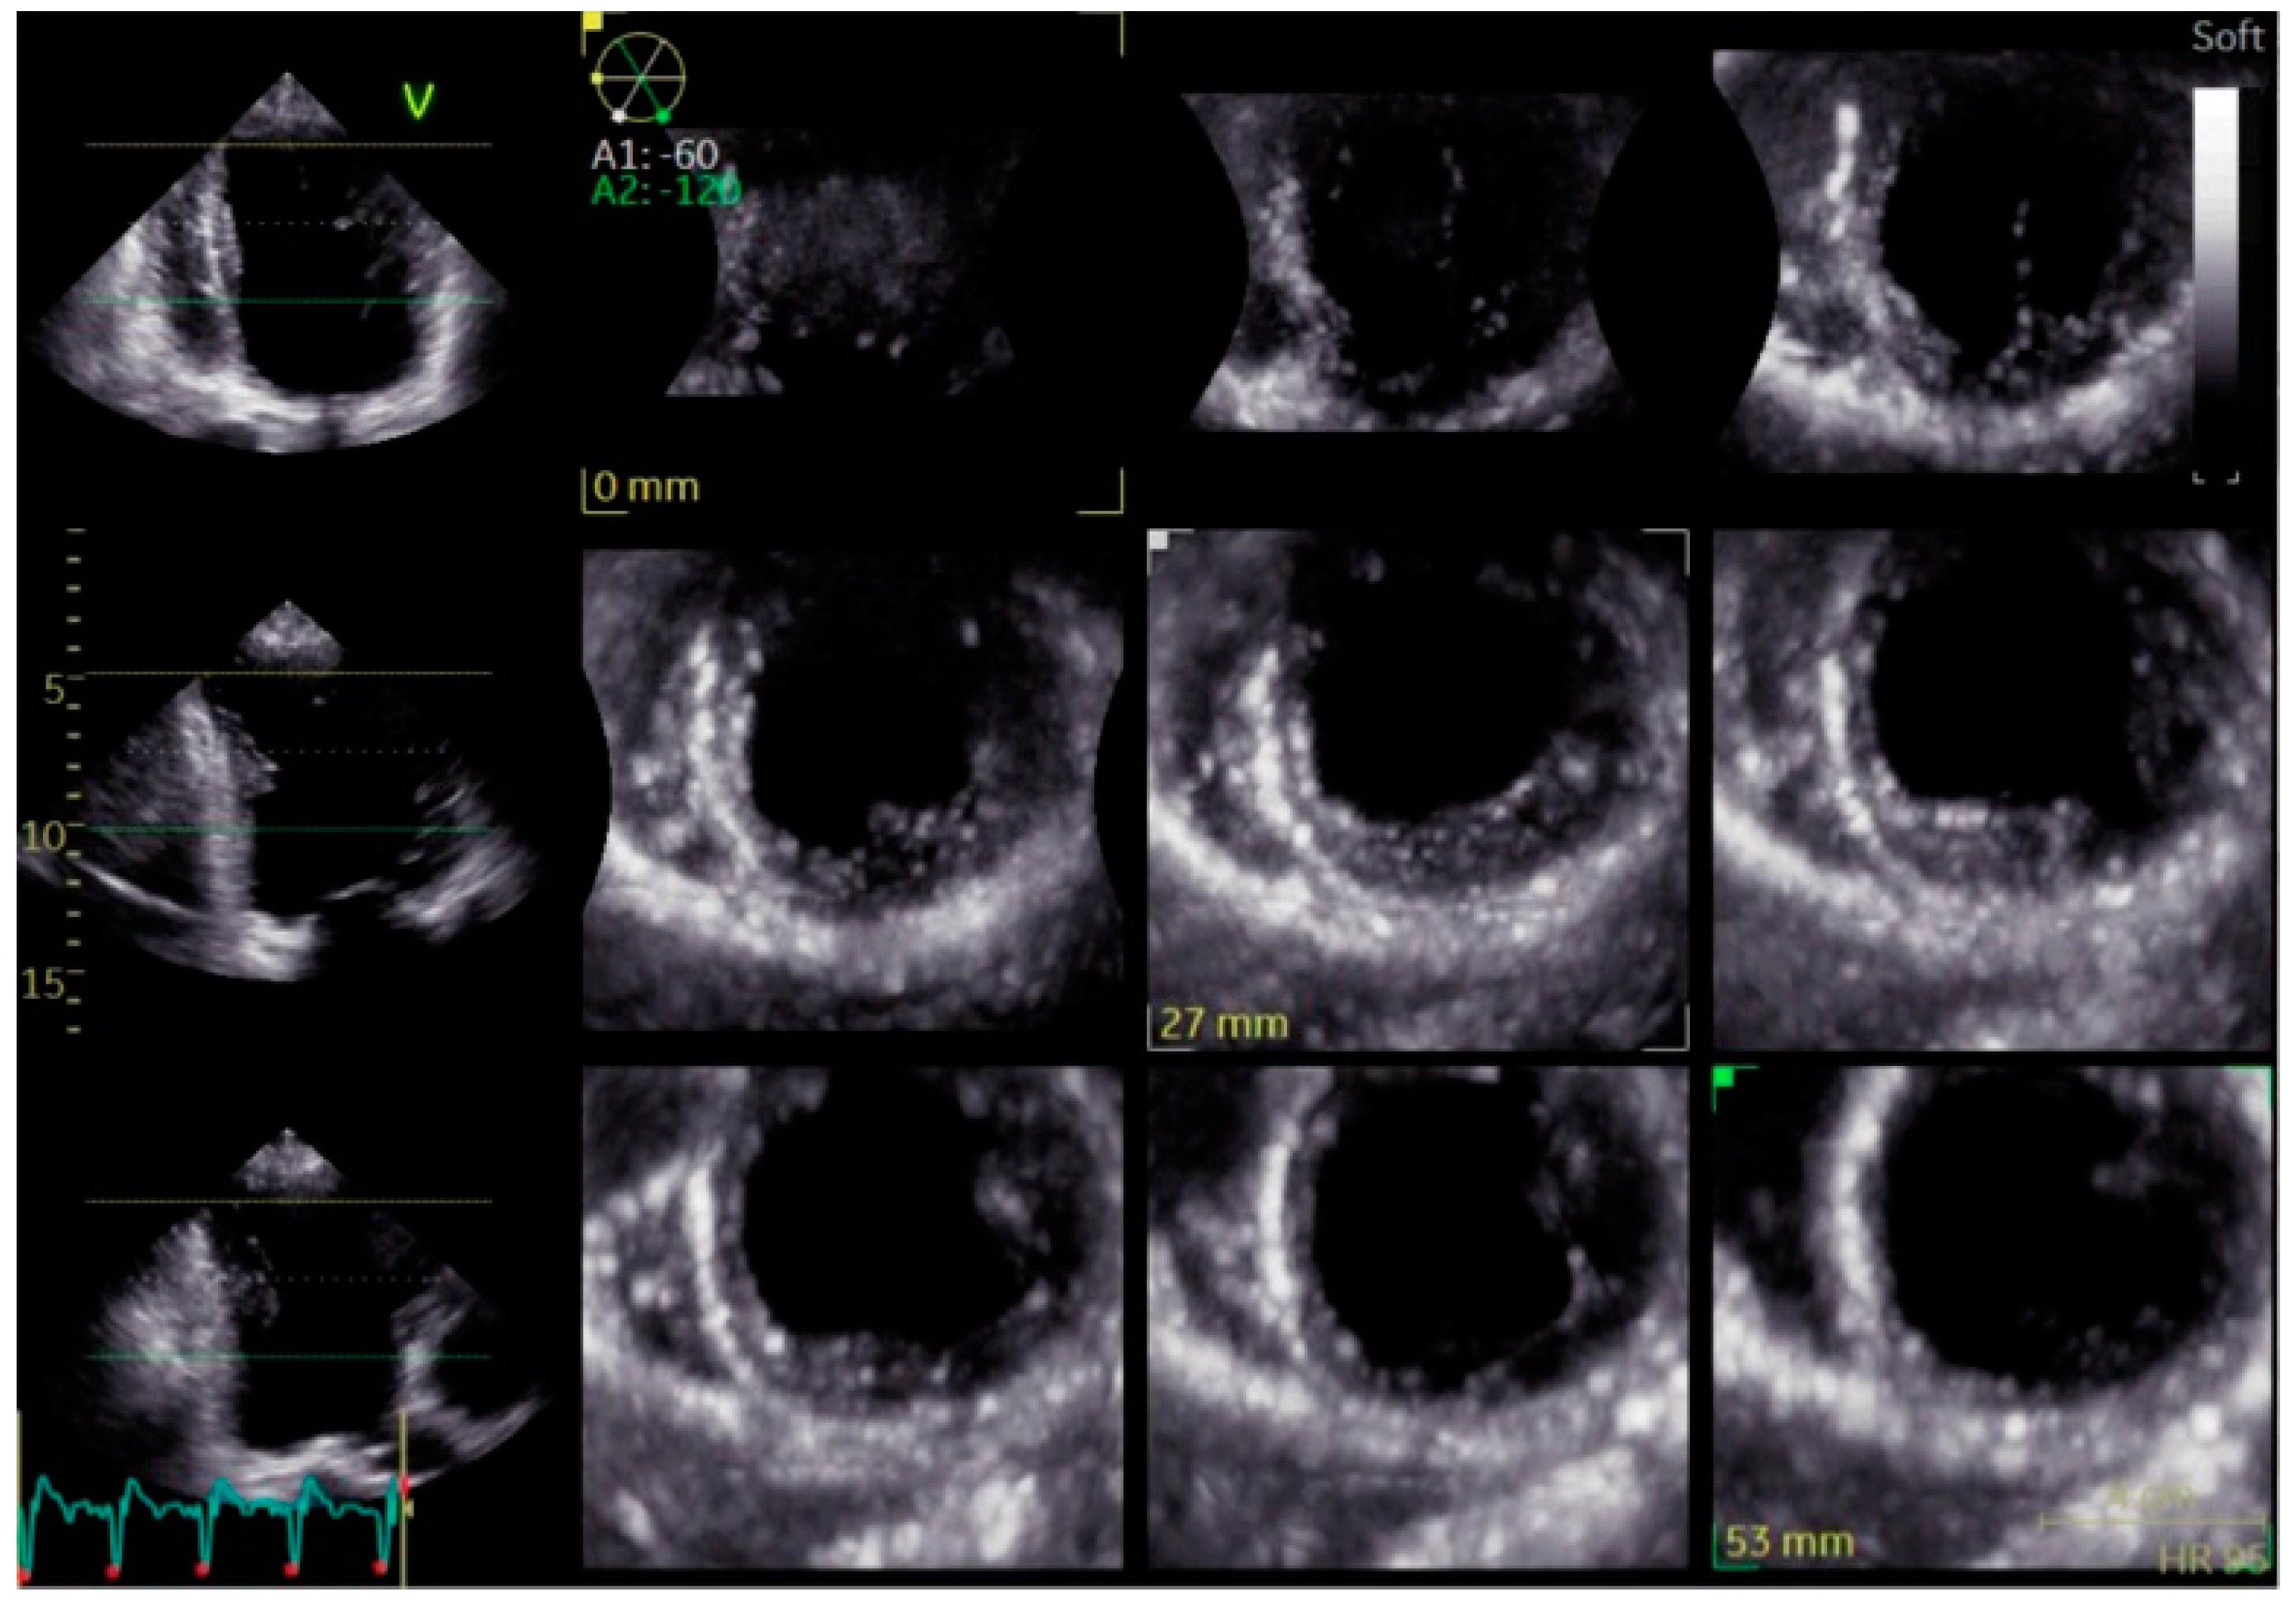

- Mei, Y.; Han, R.; Cheng, L.; Li, R.; He, Y.; Xie, J.; Wang, Z.; Wu, Y. Assessment of Cardiac Function and Ventricular Mechanical Synchronization in Left Bundle Branch Area Pacing by Speckle Tracking and Three-Dimensional Echocardiography. Am. J. Cardiol. 2023, 187, 1–9. [Google Scholar] [CrossRef]